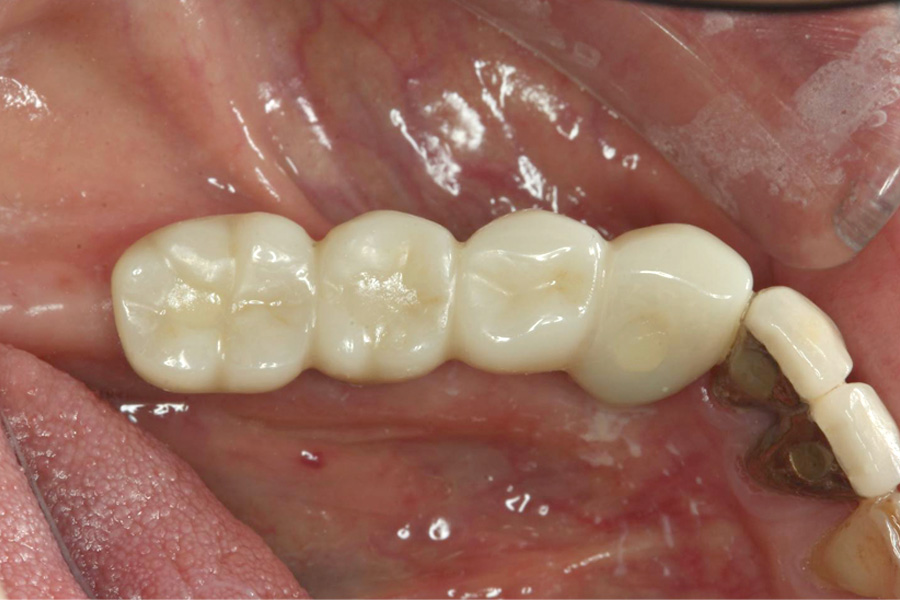

【60代女性】他院で治療した

ブリッジをインプラントで

再治療したケース

治療後

治療後症例写真

ブリッジの土台にしていた歯の保存ができなくなり、再治療を行いました。

右下3番、7番の抜歯後、右下3番、5番、6番相当部分にインプラントを3本埋入し、補綴を行いました。

治療期間

(治療回数)

約10ヶ月

治療費 約200万円

治療回数 12回

治療内容 右下奥歯抜歯、インプラント埋入(3本)